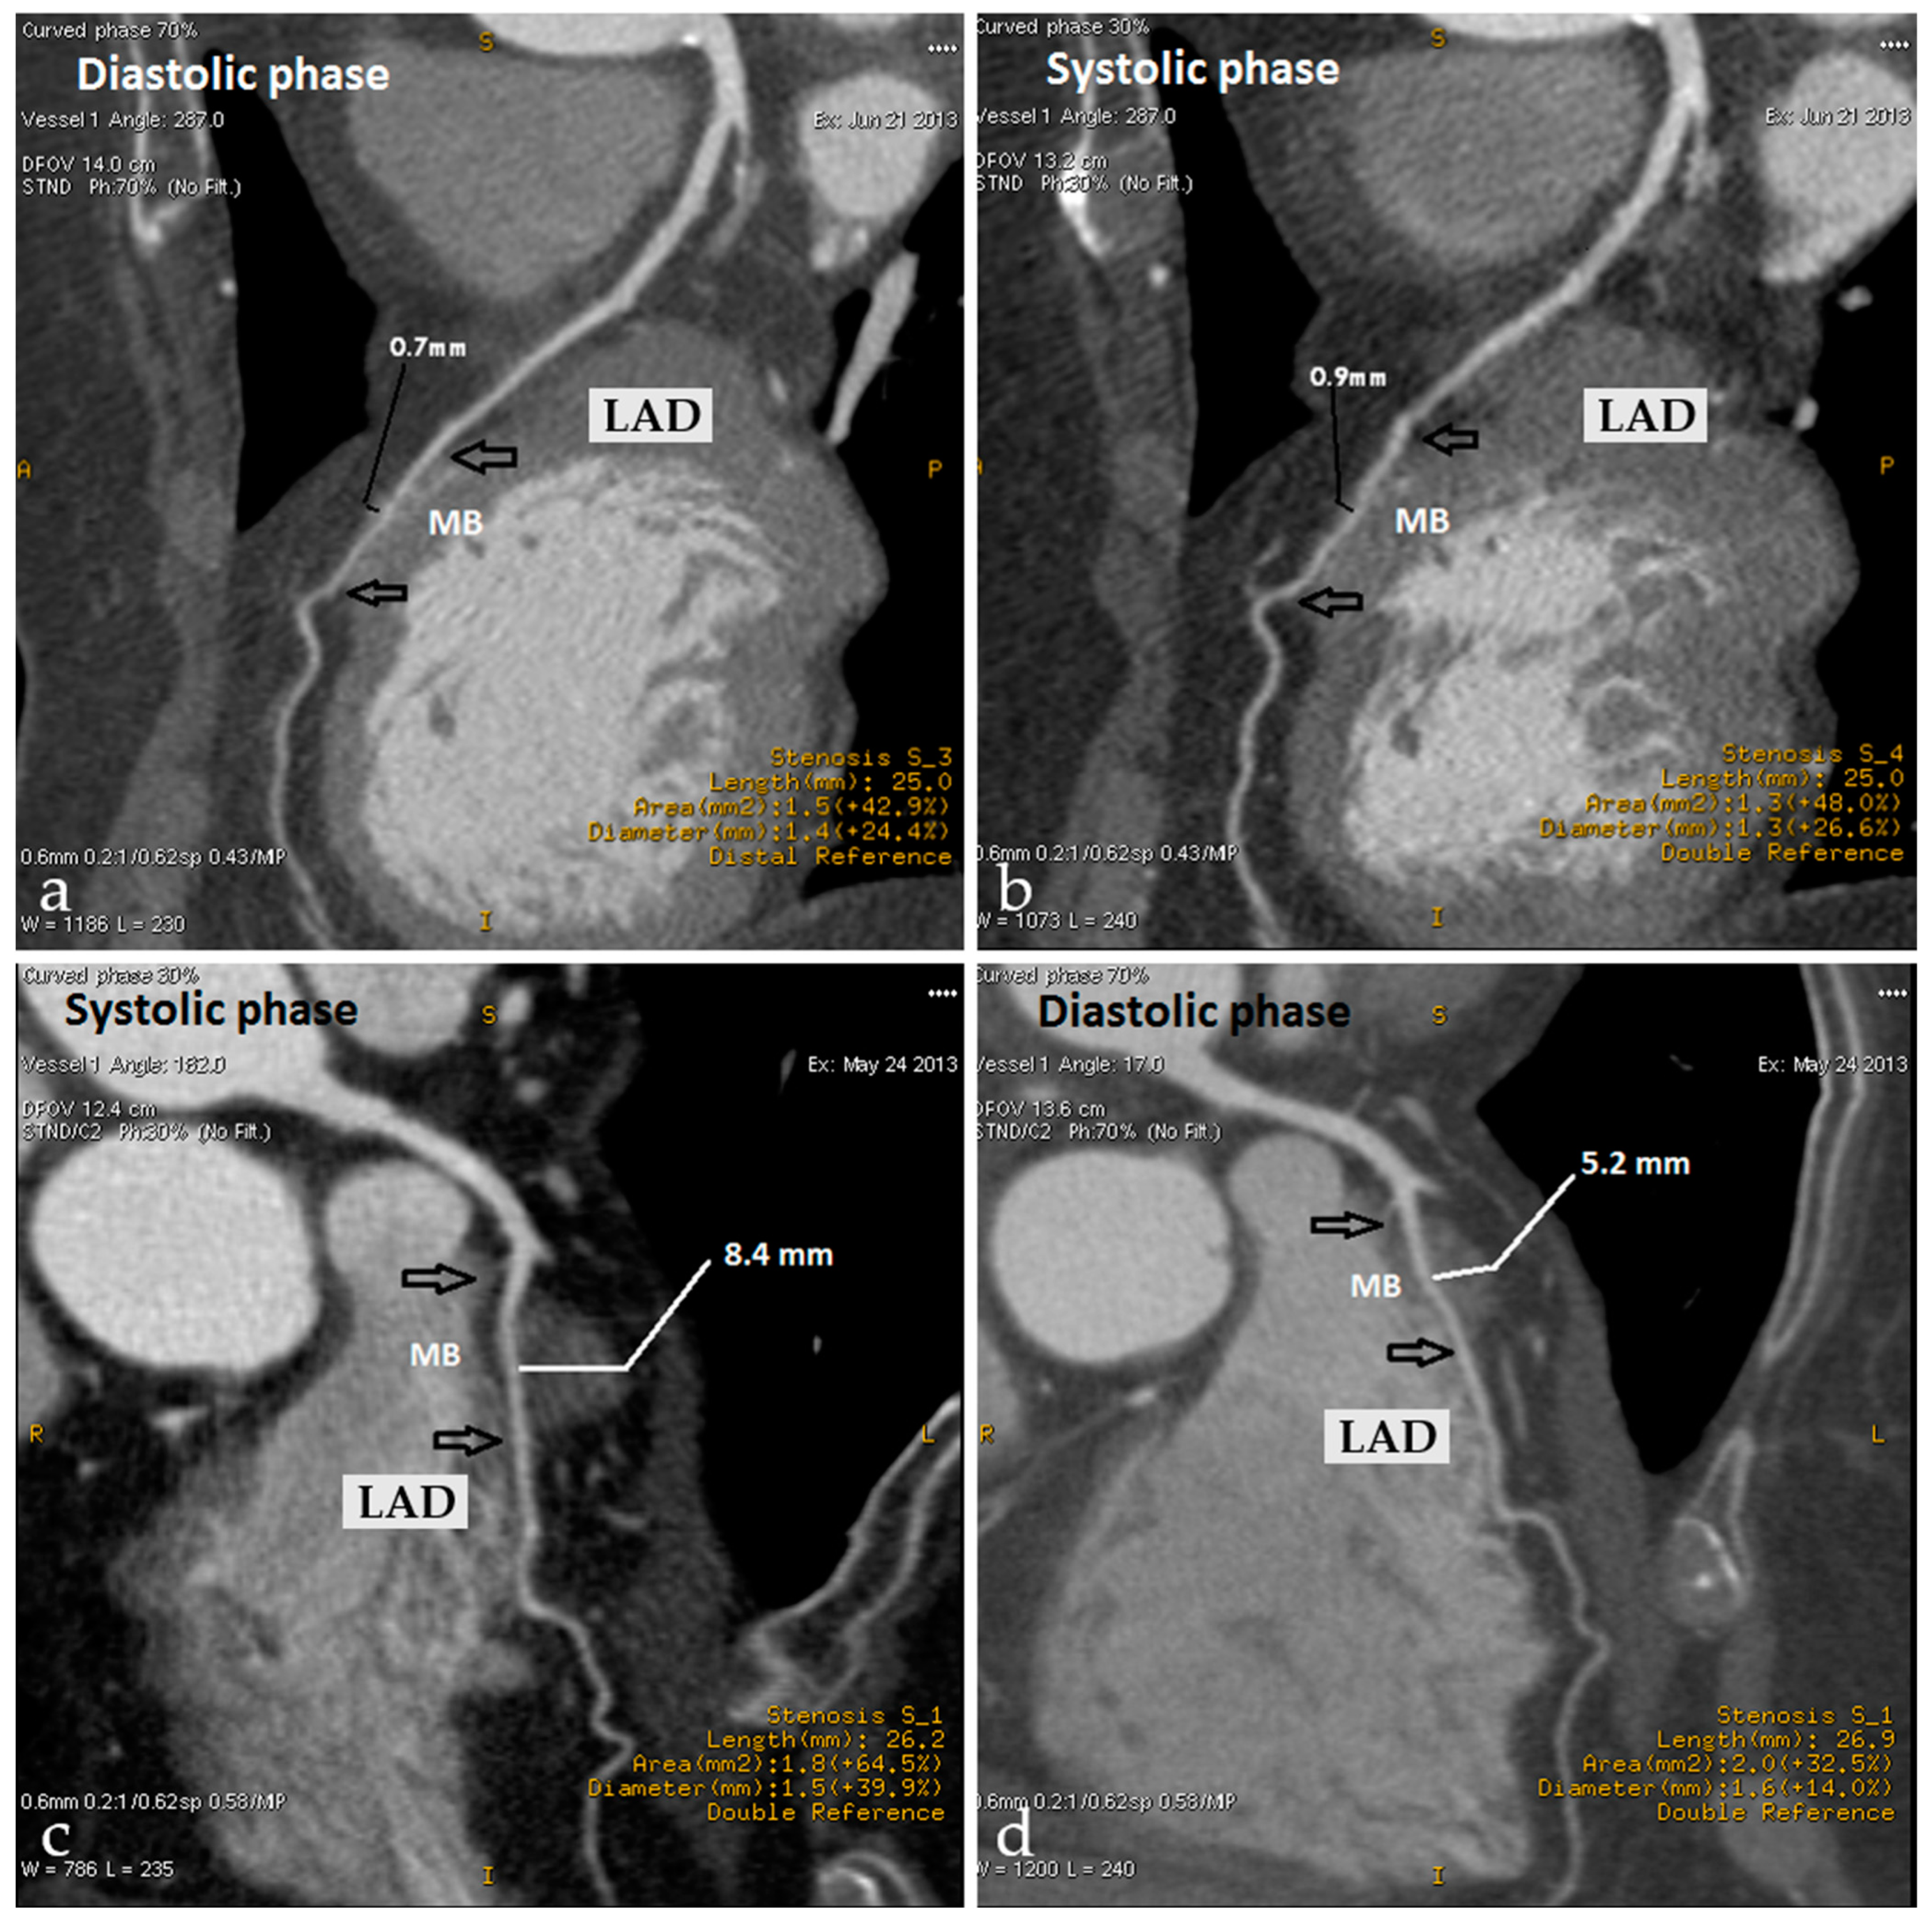

5.3. Myocardial Bridging

- Rinaldi, R.; Princi, G.; La Vecchia, G.; Bonanni, A.; Chiariello, G.A.; Candreva, A.; Gragnano, F.; Calabrò, P.; Crea, F.; Montone, R.A. MINOCA Associated with a Myocardial Bridge: Pathogenesis, Diagnosis and Treatment. J. Clin. Med. 2023, 12, 3799. [Google Scholar] [CrossRef]

- Alegria, J.R.; Herrmann, J.; Holmes, D.R., Jr.; Lerman, A.; Rihal, C.S. Myocardial bridging. Eur. Heart J. 2005, 26, 1159–1168. [Google Scholar] [CrossRef] [PubMed]

- Yuan, S.M. Myocardial Bridging. Braz. J. Cardiovasc. Surg. 2016, 31, 60–62. [Google Scholar] [CrossRef]

- Santucci, A.; Jacoangeli, F.; Cavallini, S.; d’Ammando, M.; de Angelis, F.; Cavallini, C. The myocardial bridge: Incidence, diagnosis, and prognosis of a pathology of uncertain clinical significance. Eur. Heart J. Suppl. 2022, 24, I61–I67. [Google Scholar] [CrossRef]

- Baz, R.O.; Refi, D.; Scheau, C.; Savulescu-Fiedler, I.; Baz, R.A.; Niscoveanu, C. Coronary Artery Anomalies: A Computed Tomography Angiography Pictorial Review. J. Clin. Med. 2024, 13, 3920. [Google Scholar] [CrossRef] [PubMed]

- Hayashi, T.; Ishikawa, K. Myocardial bridge: Harmless or harmful. Intern. Med. 2004, 43, 1097–1098. [Google Scholar] [CrossRef] [PubMed]

- Bourassa, M.G.; Butnaru, A.; Lespérance, J.; Tardif, J.C. Symptomatic myocardial bridges: Overview of ischemic mechanisms and current diagnostic and treatment strategies. J. Am. Coll. Cardiol. 2003, 41, 351–359. [Google Scholar] [CrossRef] [PubMed]

- Gould, K.L.; Johnson, N.P. Myocardial Bridges: Lessons in Clinical Coronary Pathophysiology. JACC Cardiovasc. Imaging 2015, 8, 705–709. [Google Scholar] [CrossRef]

- Kim, P.J.; Hur, G.; Kim, S.Y.; Namgung, J.; Hong, S.W.; Kim, Y.H.; Lee, W.R. Frequency of myocardial bridges and dynamic compression of epicardial coronary arteries: A comparison between computed tomography and invasive coronary angiography. Circulation 2009, 119, 1408–1416. [Google Scholar] [CrossRef]

- Ciampricotti, R.; el Gamal, M. Vasospastic coronary occlusion associated with a myocardial bridge. Catheter. Cardiovasc. Diagn. 1988, 14, 118–120. [Google Scholar] [CrossRef]

- Saito, Y.; Kitahara, H.; Shoji, T.; Tokimasa, S.; Nakayama, T.; Sugimoto, K.; Fujimoto, Y.; Kobayashi, Y. Relation between severity of myocardial bridge and vasospasm. Int. J. Cardiol. 2017, 248, 34–38. [Google Scholar] [CrossRef]

- Montone, R.A.; Gurgoglione, F.L.; Del Buono, M.G.; Rinaldi, R.; Meucci, M.C.; Iannaccone, G.; La Vecchia, G.; Camilli, M.; D’Amario, D.; Leone, A.M.; et al. Interplay Between Myocardial Bridging and Coronary Spasm in Patients with Myocardial Ischemia and Non-Obstructive Coronary Arteries: Pathogenic and Prognostic Implications. J. Am. Heart Assoc. 2021, 10, e020535. [Google Scholar] [CrossRef]